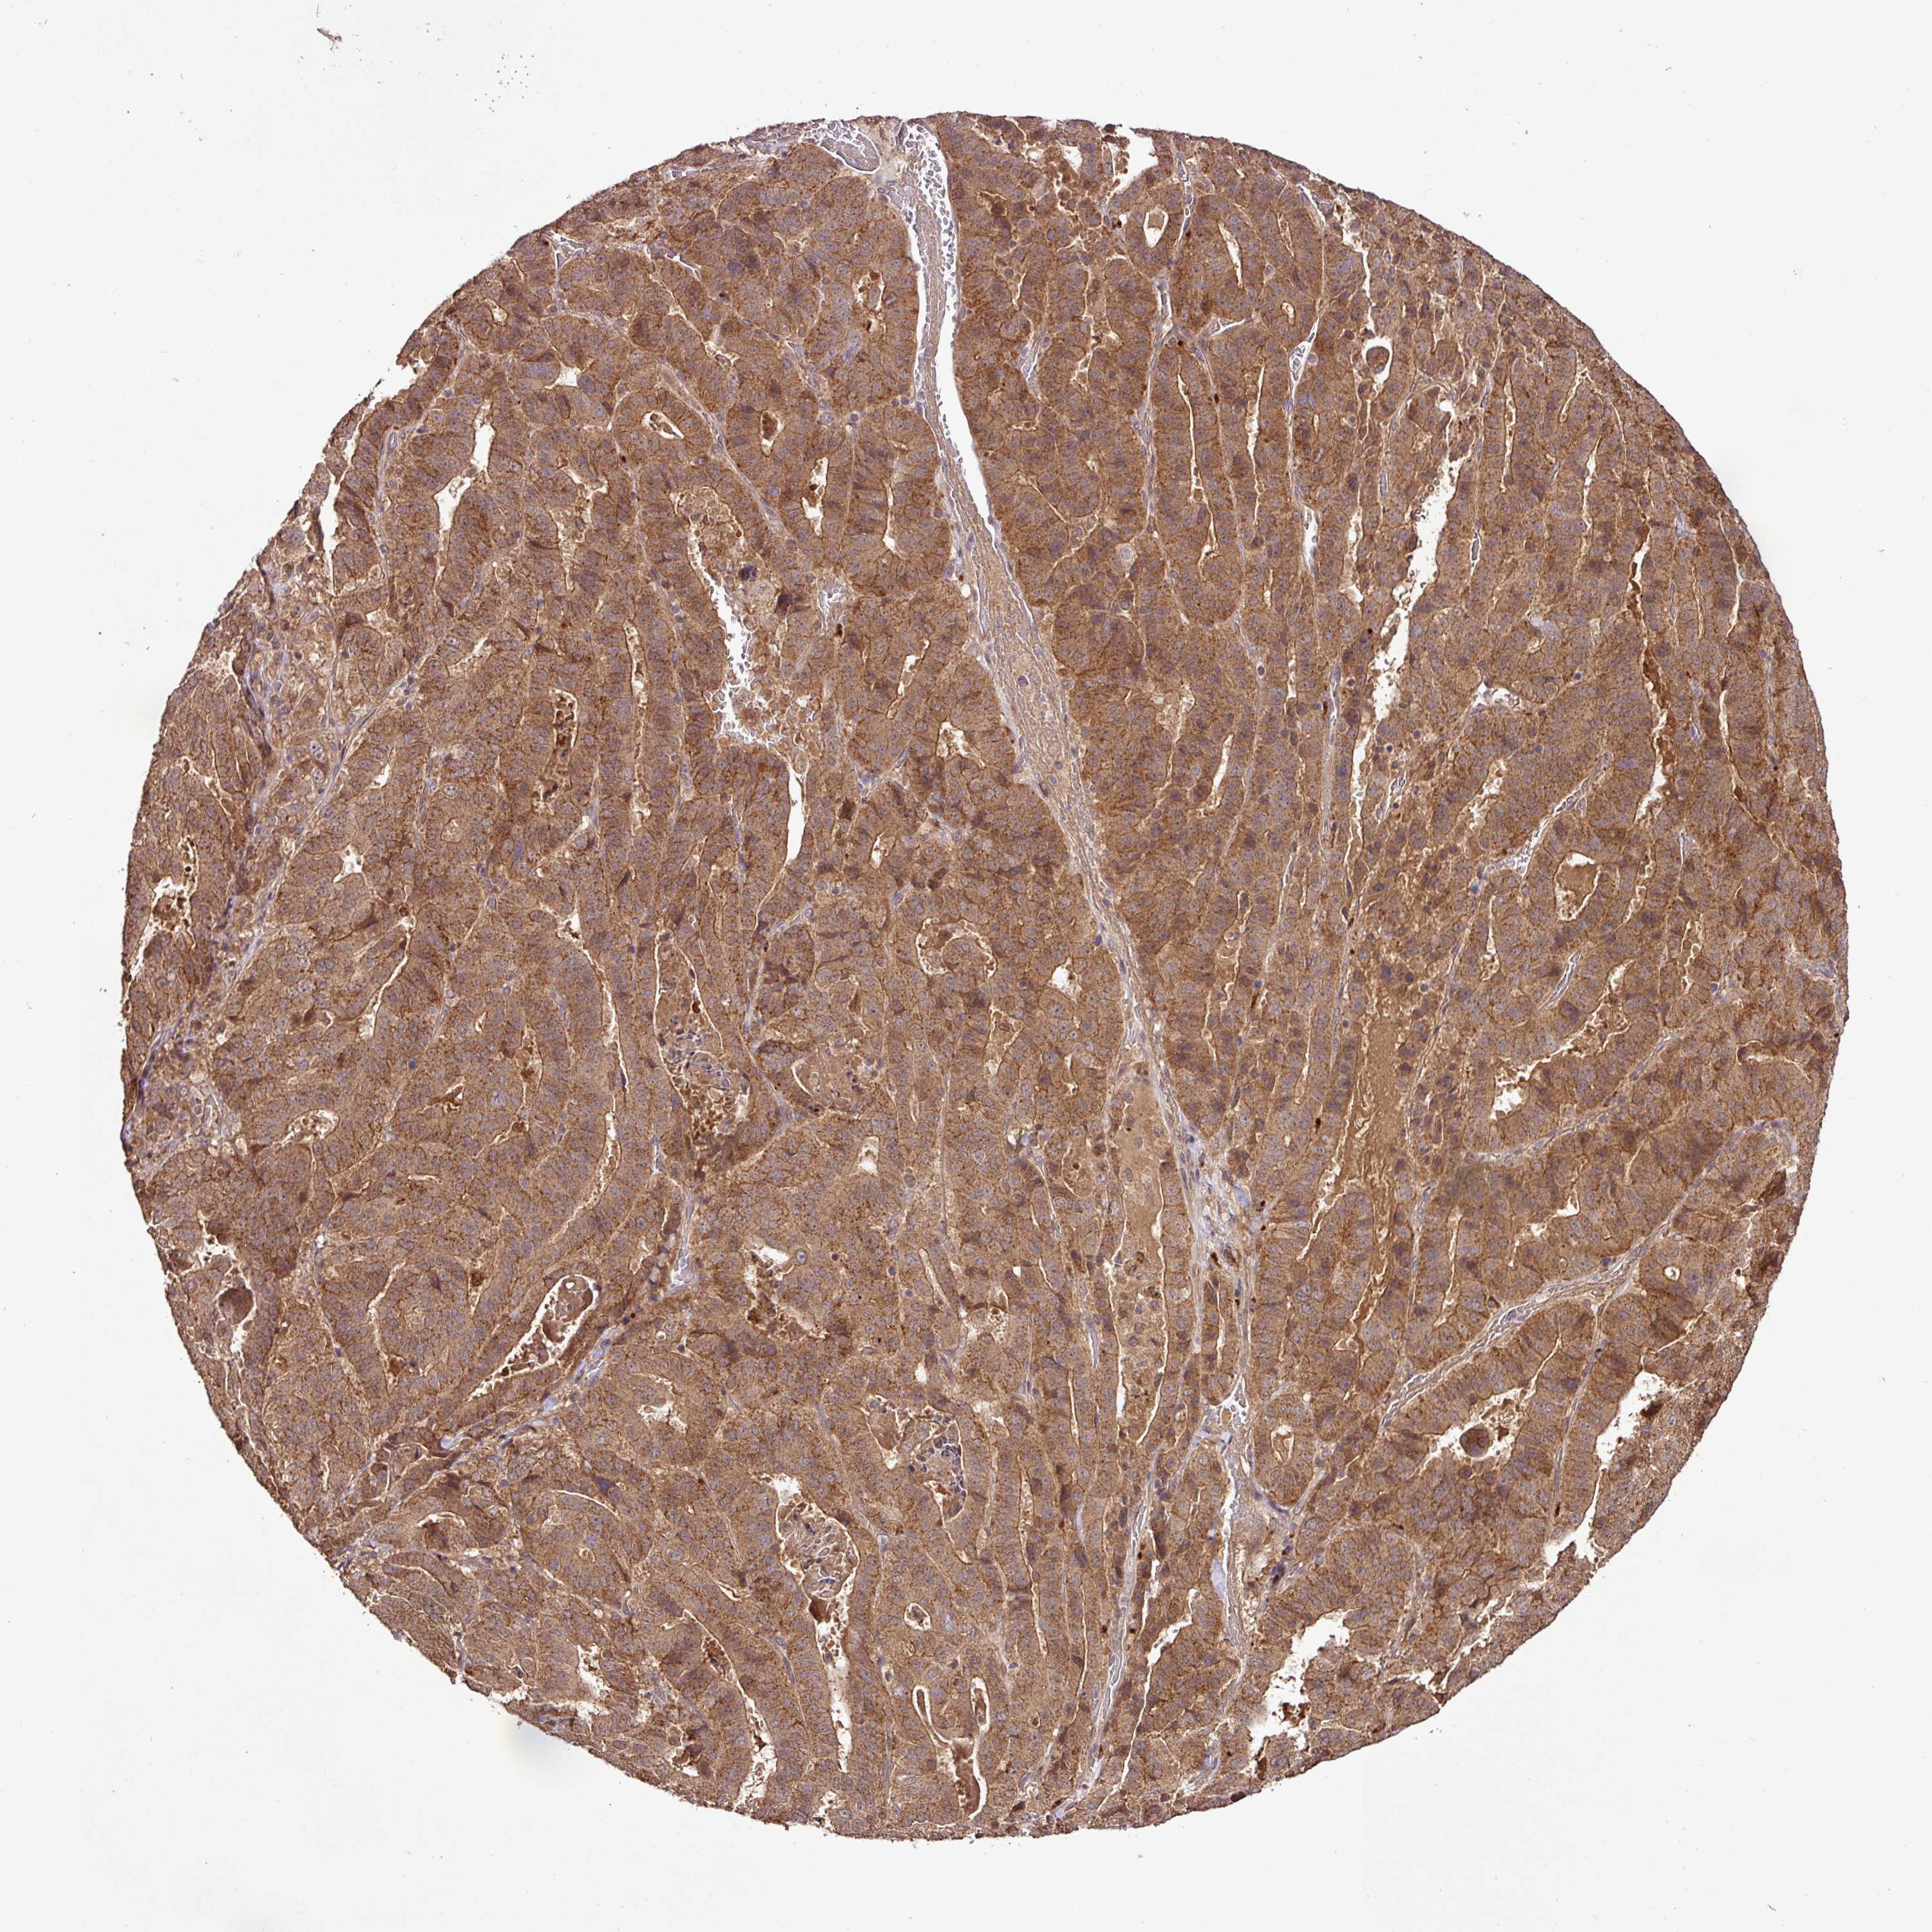

STOMACH CANCER - Protein expressioni

A mouse-over function shows sample information and annotation data. Click on an image to view it in a full screen mode. Samples can be filtered based on level of antibody staining by selecting one or several of the following categories: high, medium, low and not detected. The assay and annotation is described here.

Note that samples used for immunohistochemistry by the Human Protein Atlas do not correspond to samples in the TCGA dataset.

Antibody stainingi

Antibody staining in the annotated cell types in the current human tissue is reported as not detected, low, medium, or high, based on conventional immunohistochemistry profiling in selected tissues. This score is based on the combination of the staining intensity and fraction of stained cells.

Each image is clickable and will lead to virtual microscopy that enables deeper exploration of all samples and also displays staining intensity scores, fraction scores and subcellular localization as well as patient and tissue information for each sample.

Antibody HPA042440

Antibody HPA052209

Staining

High

Medium

Low

Not detected

Intensity

Strong

Moderate

Weak

Negative

Quantity

>75%

75%-25%

<25%

None

Location

Nuclear

Cytoplasmic/membranous

Cytoplasmic/membranous,nuclear

Adenocarcinoma, NOS